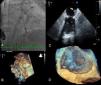

(A) Implantation of a 22 mm Amplatzer™ Cardiac Plug (ACP); (B) three-dimensional transesophageal echocardiography guidance of the procedure; (C) thrombus on atrial surface of the ACP on two-dimensional transesophageal echocardiography (white arrow); (D) three-dimensional transesophageal echocardiography showing thrombus on the device (zoom mode).

An 81-year-old woman with permanent atrial fibrillation (CHA2DS2-VASc score=5) was referred for left atrial appendage (LAA) closure. She had a history of hypertension, stage IV chronic kidney disease and chronic anemia, secondary to gastrointestinal bleeding (HAS-BLED score=3). Percutaneous LAA closure with a 22 mm first-generation device (Amplatzer™ Cardiac Plug [ACP]) was performed (Figure 1A, Video 1). The procedure was guided by three-dimensional transesophageal echocardiography (TEE) and complete occlusion was confirmed (Figure 1B, Videos 2 and 3). She was treated with aspirin 100 mg plus clopidogrel 75 mg daily for one month, clopidogrel 75 mg daily for six months, and no antithrombotic drug thereafter.

By protocol, follow-up TEE was performed at 12 months and revealed a large mobile thrombus attached to the atrial surface of the ACP (Figure 1C and D, Videos 4 and 5).